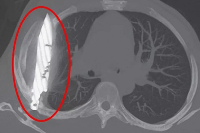

Магнитно-резонансная томография (МРТ):один из самых эффективных методов диагностики заболеваний